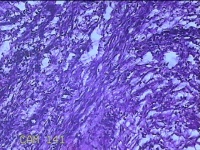

左侧卵巢囊肿⑴

性别

女

年龄

34岁

临床诊断

左侧卵巢子宫内膜异位囊肿

一般病史

下腹痛3小时入院。

标本名称

大体所见

灰白暗红色囊性肿物8x2.5x0.7cm一个,表面糜烂,部分已切开,囊内容物已流失,囊壁厚0.1cm。